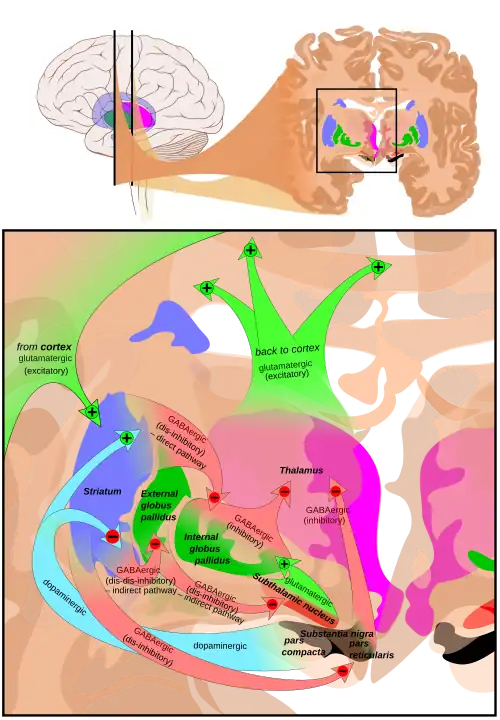

The exact mechanisms of DBS are complex and not fully understood, though it is thought to mimic the effects of lesioning by disrupting pathologically elevated and oversynchronized informational flow in misfiring brain networks.[5][6][7] As opposed to permanent ablation, the effect can be reversed by turning off the DBS device.[8] Common targets include the globus pallidus, ventral nuclear group of the thalamus, internal capsule and subthalamic nucleus. It is one of few neurosurgical procedures that allows blinded studies,[9] though most studies to date have not taken advantage of this discriminant.[10]

DBS is used to manage Parkinson's disease symptoms that are resistant to medication.[20][30] The ideal candidate for DBS is one that does not have dementia, is not severely depressed, and who does not have falls while being in their best on-drug state, but who do have disabling motor fluctuations or dyskinesias that necessitate bilateral surgery.[1] It is treated by applying high-frequency (> 100 Hz) stimulation to target structures in the deep subcortical white matter of the basal ganglia. Frequently used targets include the subthalamic nucleus (STN), globus pallidus internus (GPi) and ventrointermediate nucleus of the thalamus (VIM). Neurostimulation can be considered for people who have Parkinson's with motor fluctuations and tremors inadequately controlled by medication, or to those who are intolerant to medication as long as they do not have severe neuropsychiatric problems.[31] A >30% degree of symptom responsiveness to dopamine is a strong predictor of a good response to DBS surgery, though it is not mandatory. This has led most centers to require evaluation both on and off dopamine prior to the procedure to increase the likelihood of success.[32] DBS is not currently considered to be a disease-modifying treatment.[33] Shorter disease duration pre-operatively tends to lead to better results after surgery. The response from DBS is only as good as the patient's best "on" time, with the exception of tremor, which may show greater improvement than that seen with medication.[34]

There is little evidence to suggest that DBS in patients with movement disorders restores normal basal ganglia functions, for example, its roles in movement or learning. Instead, it appears that high-frequency DBS mitigates abnormal basal ganglia output into a more tolerable pattern, helping to restore downstream network function. In support of this theory is the observation that in a normal healthy brain, all basal ganglia connections are inhibitory except for those from the STN.[190]

The STN, the most common nucleus targeted in Parkinson's, integrates motor, cognitive, and emotional information to orchestrate complex behaviors. Furthermore, fMRI studies showed that the STN is involved in emotional processes such as amusement, disgust, sexual arousal, and maternal and romantic love. On fMRI STN-DBS reversed the hypometabolism in motor, associative, and limbic prefrontal areas observed in Parkinson's disease and the diffuse hypermetabolism of the prefrontal cortex. The functional deafferentation of the STN induced by DBS seems to improve executive functions, but reduction of reaction time hastens the decision, which could lead to impulsive and erroneous choices.[1]

In 1990, the first models of basal ganglia function were mapped out based on the segregated circuits in its thalamocortical network. During this time pallidotomies were reintroduced for individuals with advanced PD and severe levodopa induced dyskinesia. In 1998, neurostimulation to the STN was first attempted for PD and two years later to the GPi for dystonia.[179]